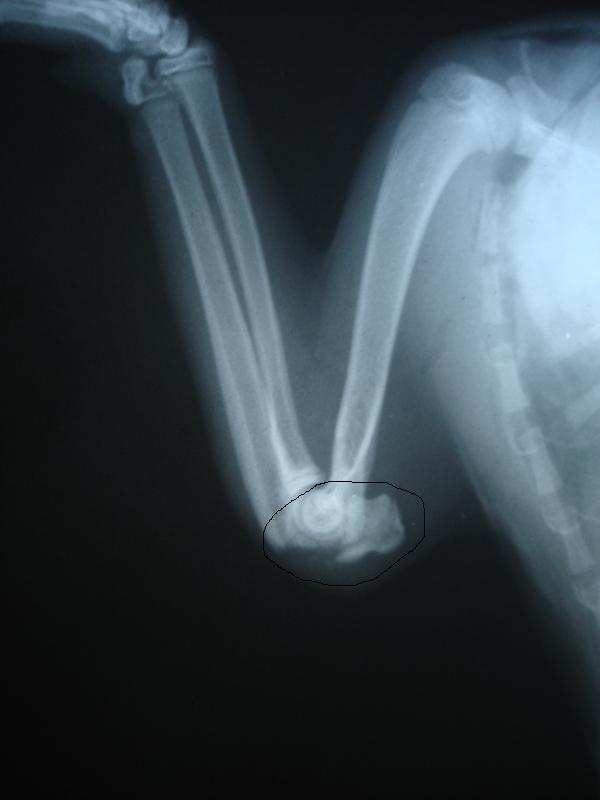

У меня все как обычно: пошла в магазин, смотрю по сторонам, вижу в сугробе, в самой глубине что-то черное......... пригляделась, котенок. Лежит, не шевелится, живой, но не вылазит. Вытащила, не ходит. Свозили ребенка в ЦВК на рентген, итог: Парень месяцев 5ти. Перелом заднего бедра, но он сам срастется сказали, сломаны зубы, но это не беда. Самое плохое то, что передняя лапка сломана и требует операции и как можно скорее. Локтевой бугор прям торчит в сторону. Нам необходимо ставить спицы. Стоит операция 7т.р. Я в данный момент не располагаю такой суммой, могу выделить на ребенка тысячи 2 максимум. Сейчас котенок временно поселился у моей подруги, принесла ему лежанку, он ее оценил, писает, какает, кушает с удовольствием. Снабдила ребенка кормом, наполнителем, мисками, лотком, лежаком. Но полную сумму на операцию я точно не потяну

Фото рентгена выложу завтра, т.к. щас темно и фото не получится, а завтра утром на окне сфоткаю. И котофея завтра по фотаю по лучше, сегодня все наспех как то.